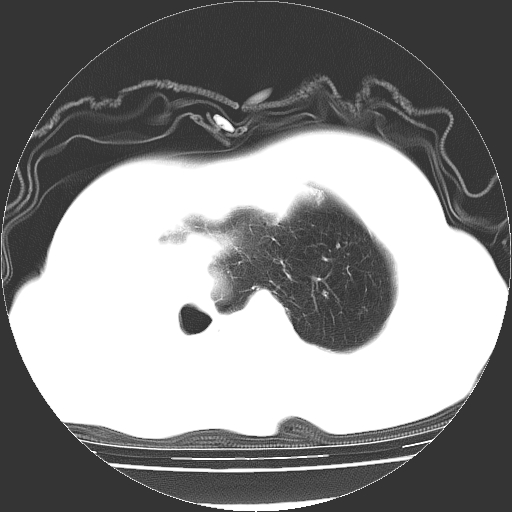

标题: CT23991:女,72岁,咳嗽、憋气一周。 [打印本页]

女,72岁,咳嗽、憋气一周,十年前曾患肺结核及胸膜结核。

右侧毁损肺,右侧纵隔疝,左肺代偿!

1.右侧损毁肺伴胸膜钙化,2.左肺小结节灶,良性可能大,注意复查。3.肝脏左叶囊肿。4.先天性一侧肺不发育待出外(右侧胸廓无明显塌陷)。对比原片应该非常有帮助。

右侧肺毁损,左肺代偿性肺气肿,纵隔疝。